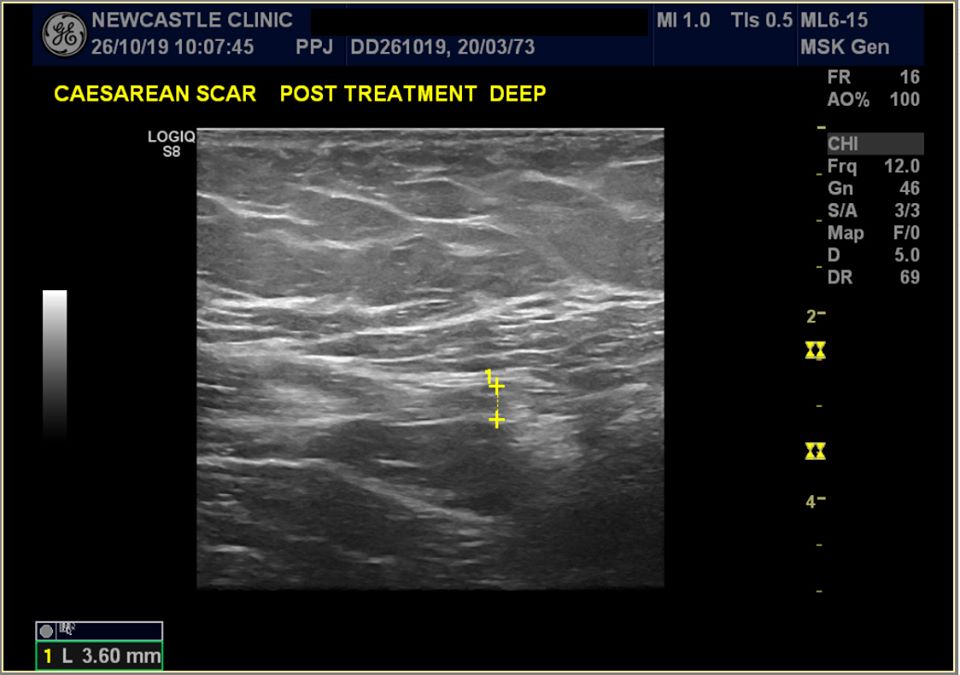

Ultraljudsbilder

Efter behandling var det bara 3,6 mm djupt.